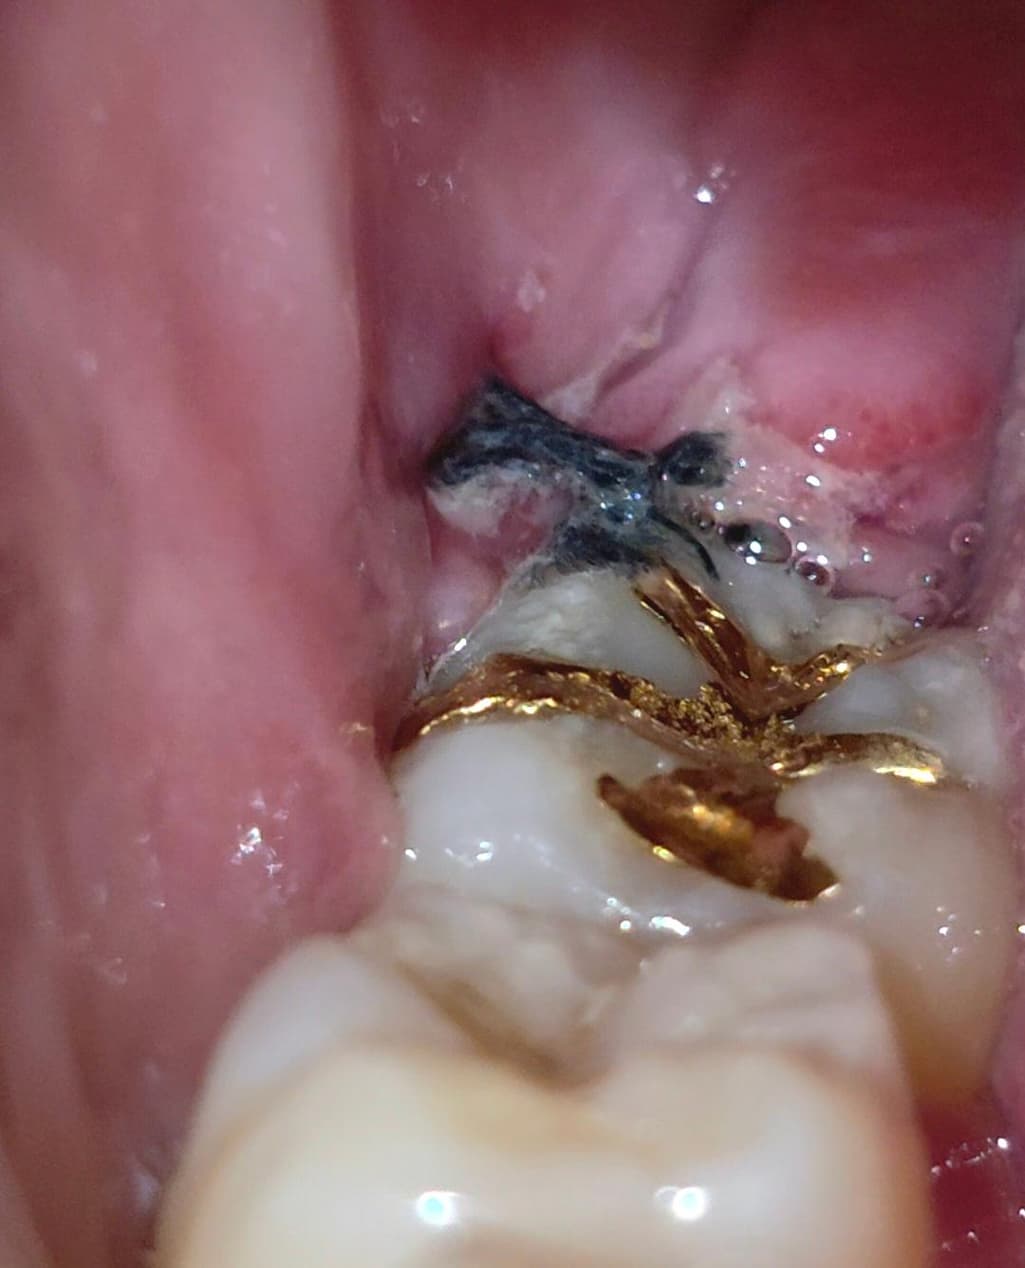

8월 13일(수요일) 09시에 대학병원에서 우측하악(48번)수평매복사랑니 발치하고, 8월 17일(일요일) 09시 사진인데(4일차), 정상적으로 치유되고 있는 과정인지 사진상으로도 확인가능할까요? 감사합니다.

사지상으로 보면 잘 아물고 잇는거 같습니다. 잇몸이 치유되면서 생기는 자연스러운 현상이니 자극만 가지 않도록 해주세요.

매복된 사랑니를 발치하고 나면 잇몸 손상이 크기 때문에 통증이 있거나 불편감이 있을 수 있습니다. 사진으로 봤을 경우에는 크게 문제가 있는 것으로 보이진 않습니다. 사랑니를 발치했다면 발치한 부위가 자극되지 않도록 하는 것이 좋습니다.

사진상 염증 등의 문제는 보이지 않습니다. 지금처럼만 관리해주셔도 잘 나을 것 같습니다.